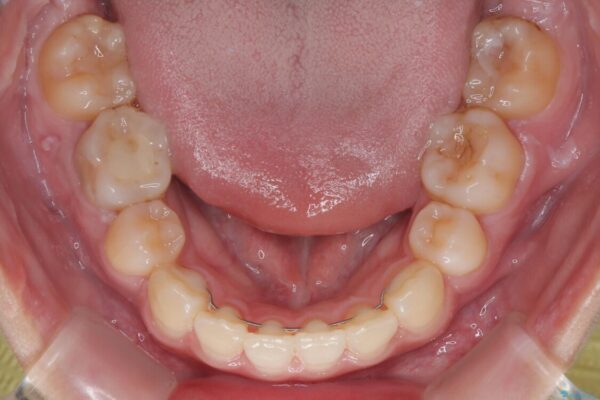

治療後

• 転勤でも安心して治療継続 抜歯スペース閉鎖と深い噛み合わせ改善のワイヤー矯正 治療後画像